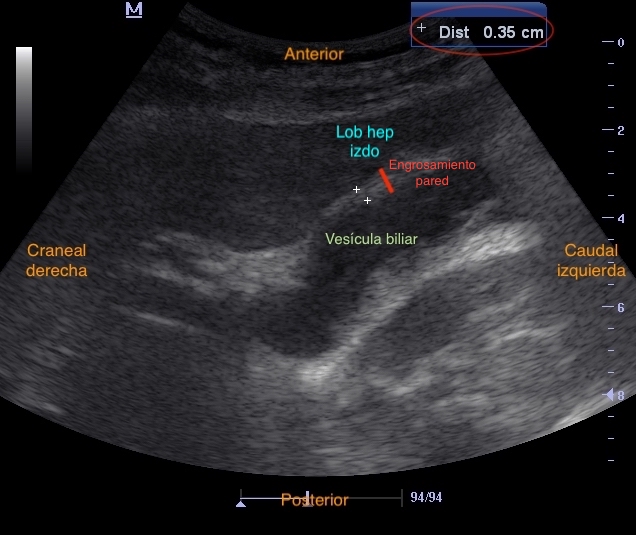

Se visualiza vesícula biliar con contenido hiperecogénico en su interior sugestivo de cálculos biliares, pared anterior engrosada (0,35 mm), con líquido perivesicular y fenómeno de ring-down en su interior (posible neumobilia). Colédoco distal dilatado, con signo del doble cañón, sin clara dilatación de conductos biliares intrahepáticos.